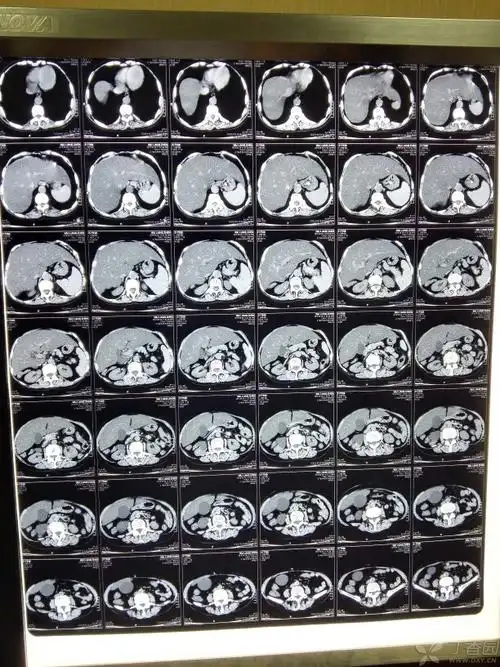

脂肪肝 - 普通外科讨论版 -丁香园论坛